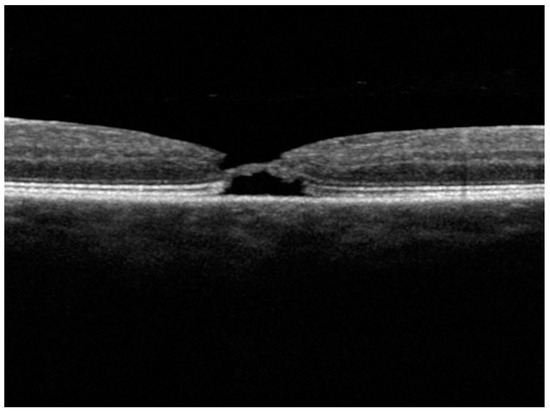

3.1.1. Patient 1, Left Eye

| 1 | No | No | Yes | Yes | Yes | Yes | FTMH | 30 | 4 | - | Yes | Yes | No | No |